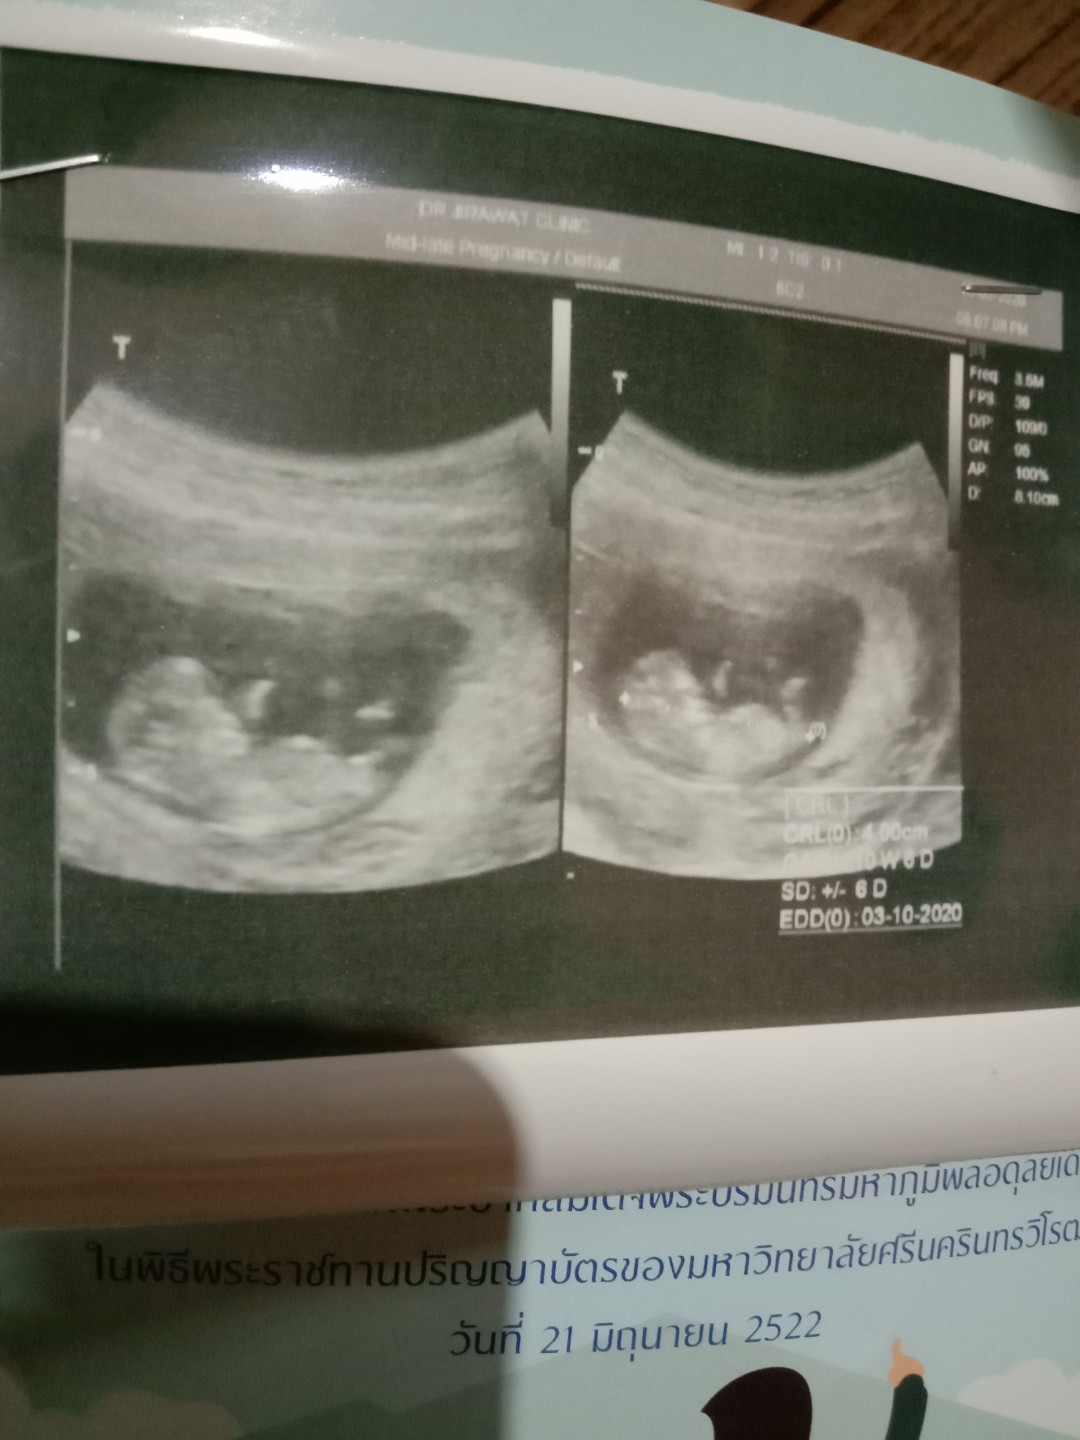

ซาวด์ตอน18วีคค่ะ

ของเราตอน10w+3